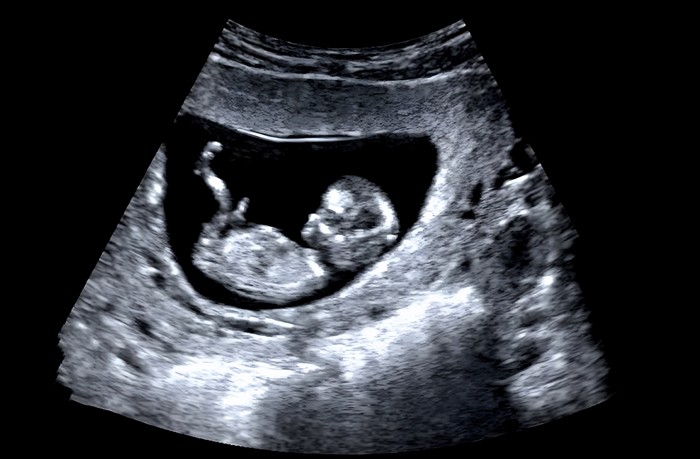

만 40세 이후 자연임신 확률은 일반적으로 10퍼센트 미만으로 낮아지며, 45세 이상에서는 1퍼센트 수준에 그친다. 자연임신이 가능한 경우라도 유산 위험, 염색체 이상, 임신중독증 등 다양한 합병증 가능성이 높아진다. 따라서 고령 임신 시 산전 검사 및 정기적인 모니터링이 필수적이다.

고령 임신은 임신 유지뿐 아니라 출산 과정에서도 주의가 필요하다. 조산 위험과 제왕절개율이 높아지는 만큼, 출산 전까지 철저한 산전 관리가 중요하다. 특히 고혈압, 당뇨, 갑상선 질환 등 기저질환이 있는 경우에는 산부인과와의 협진이 권장된다.